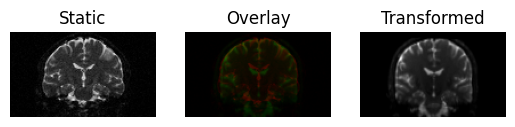

This results in a slight shear and scale

transformed = affine.transform(moving)

<Figure size 640x480 with 3 Axes>

Registration result with an affine transform, using Mutual Information.